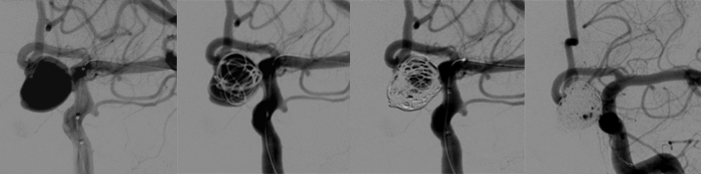

脳動脈瘤コイル塞栓術は、カテーテルにより脳動脈瘤の中にプラチナ製のコイルを挿入し破裂を防ぐ方法です。コイルが母血管にはみ出さないように母血管にバルーンやステントを置くこともあります。最近では、フローダイバーターという網目の細かいステントを母血管に留置する方法もあります。

太ももの付け根の動脈よりガイディングカテーテルを挿入し、

1) 動脈瘤内にマイクロカテーテルを挿入

2) 動脈瘤内大きさに応じたプラチナ製のコイルで塞栓(このときにコイルが母血管にはみださないようにバルーン(風船)やステントを使用することがあります)

3) 径の大きい長いコイルから径の小さい短いコイルを何本か使って動脈瘤内に血流が残らないように塞栓

4) 手技が終了したらカテーテルを抜去